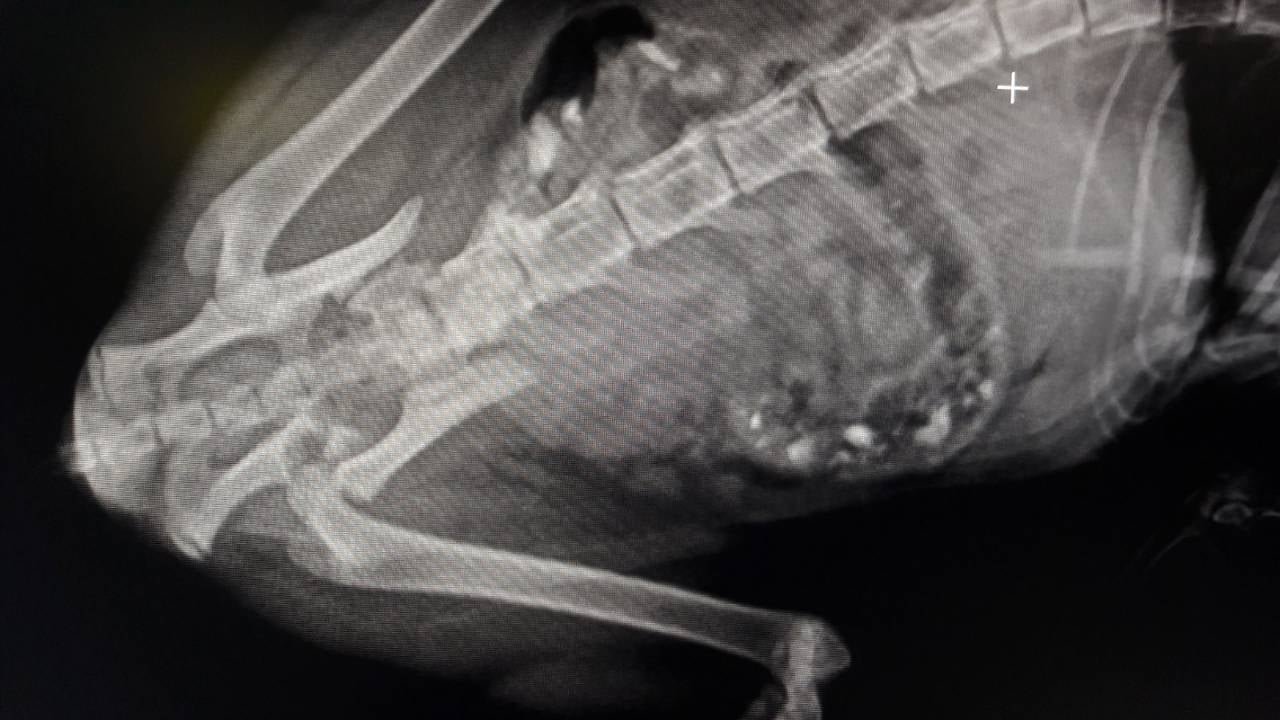

Хвостатого принесли в клинику, где его обследовали ветеринары. Оказалось, что у животного травмы, характерные для падения с высоты: перелом вертлужной впадины, лонного сращения и крестцовой кости, черепно-мозговая травма, гематома глаза. Об этом сообщает Информатор со ссылкой на публикацию Ольги Уманчик.